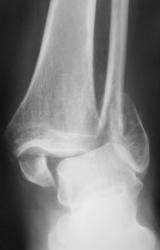

Перелом обеих лодыжек со смещением, наружно-пронационный вывих стопы.

А передний край пилона разве не сломан? Или это медиальная лодыжка наслаивается?